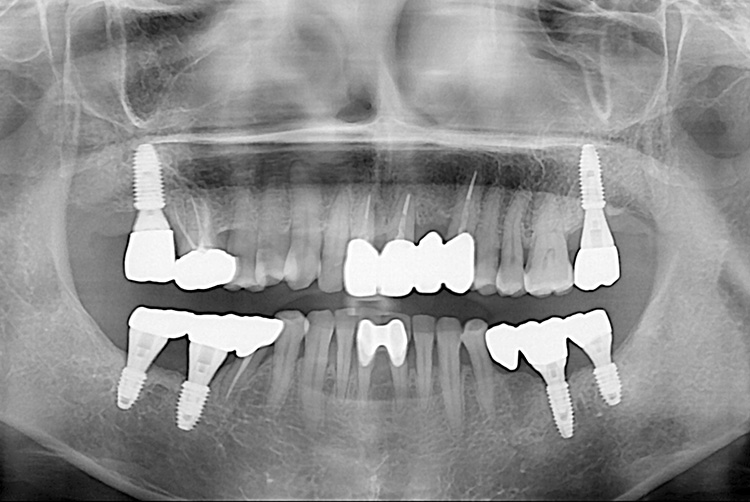

[임플란트] 임플란트

치료전 : 2018-01-08

치료후 : 2020-03-09

세종치과는 많은 환자와 다양한 케이스를 바탕으로 항상 편안한 임플란트 수술을 제공하고자 노력하고,

오래동안 튼튼히 쓸 수 있는 임플란트 수술을 가장 큰 목표로 삼고 있습니다